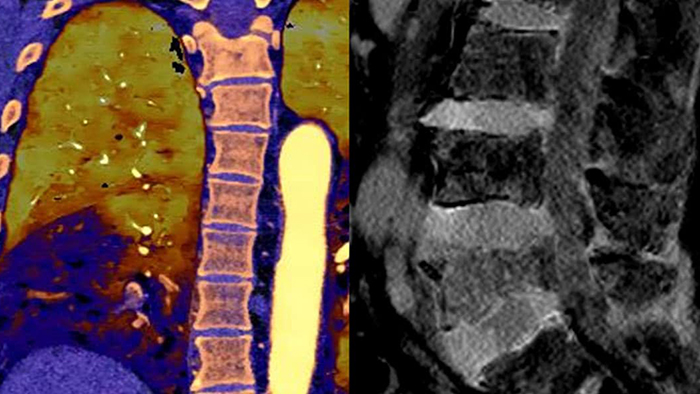

Unlike traditional CT images, spectral-detector CT images capture spectral information 100% of the time —without special planning or set-up. That means you can analyze the spectral data in any image retrospectively, using a variety of spectral viewing tools. You can, for example, adjust the monoenergetic level or get Zeffective maps.

Can you see the difference?

Move the slider to reveal spectral results when compared to conventional CT.

Spectral detector simultaneously absorbs and differentiates high and low energy from a single polyenergetic X-ray beam. Spectral results are acquired within a single scan without the need for special modes.

Spectral Results Anytime, Anywhere. Single DICOM entity contains sufficient information for retrospective analysis.

Detector-based spectral CT simultaneously absorbs high and low energies in the same time and space.

Spectral CT helps me objectively differentiate contrast staining from hemorrhage, obviating the need for additional follow up scanning and prolonged patient observation, which can result in reduced costs and radiation exposure to patients.1,2